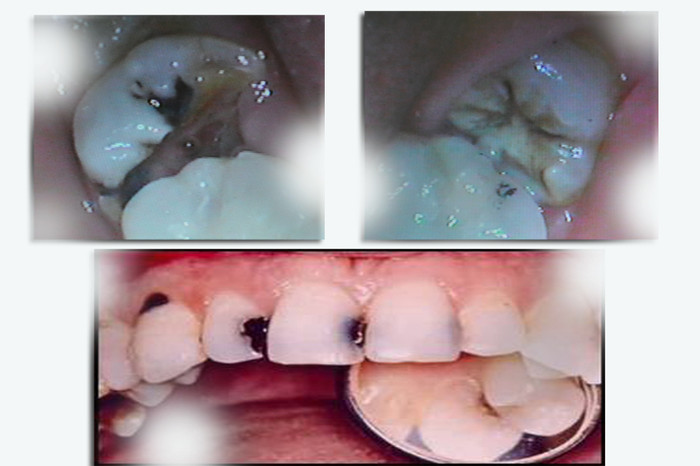

| Nếu bạn bị sâu răng, bạn sẽ biết ngay? Đó là một hiểu lầm tai hại. Ở giai đoạn đầu của sâu răng thì sẽ không có biểu hiện triệu chứng gì. Đến khi bạn cảm nhận được nỗi đau của những chỗ sâu răng gây ra thì lúc đó sâu răng đã ở mức độ nặng và gây tổn hại dây thần kinh rất nhiều rồi. Vậy nên hãy thường xuyên tự kiểm tra răng để phát hiện sớm các bệnh ở răng miệng. |